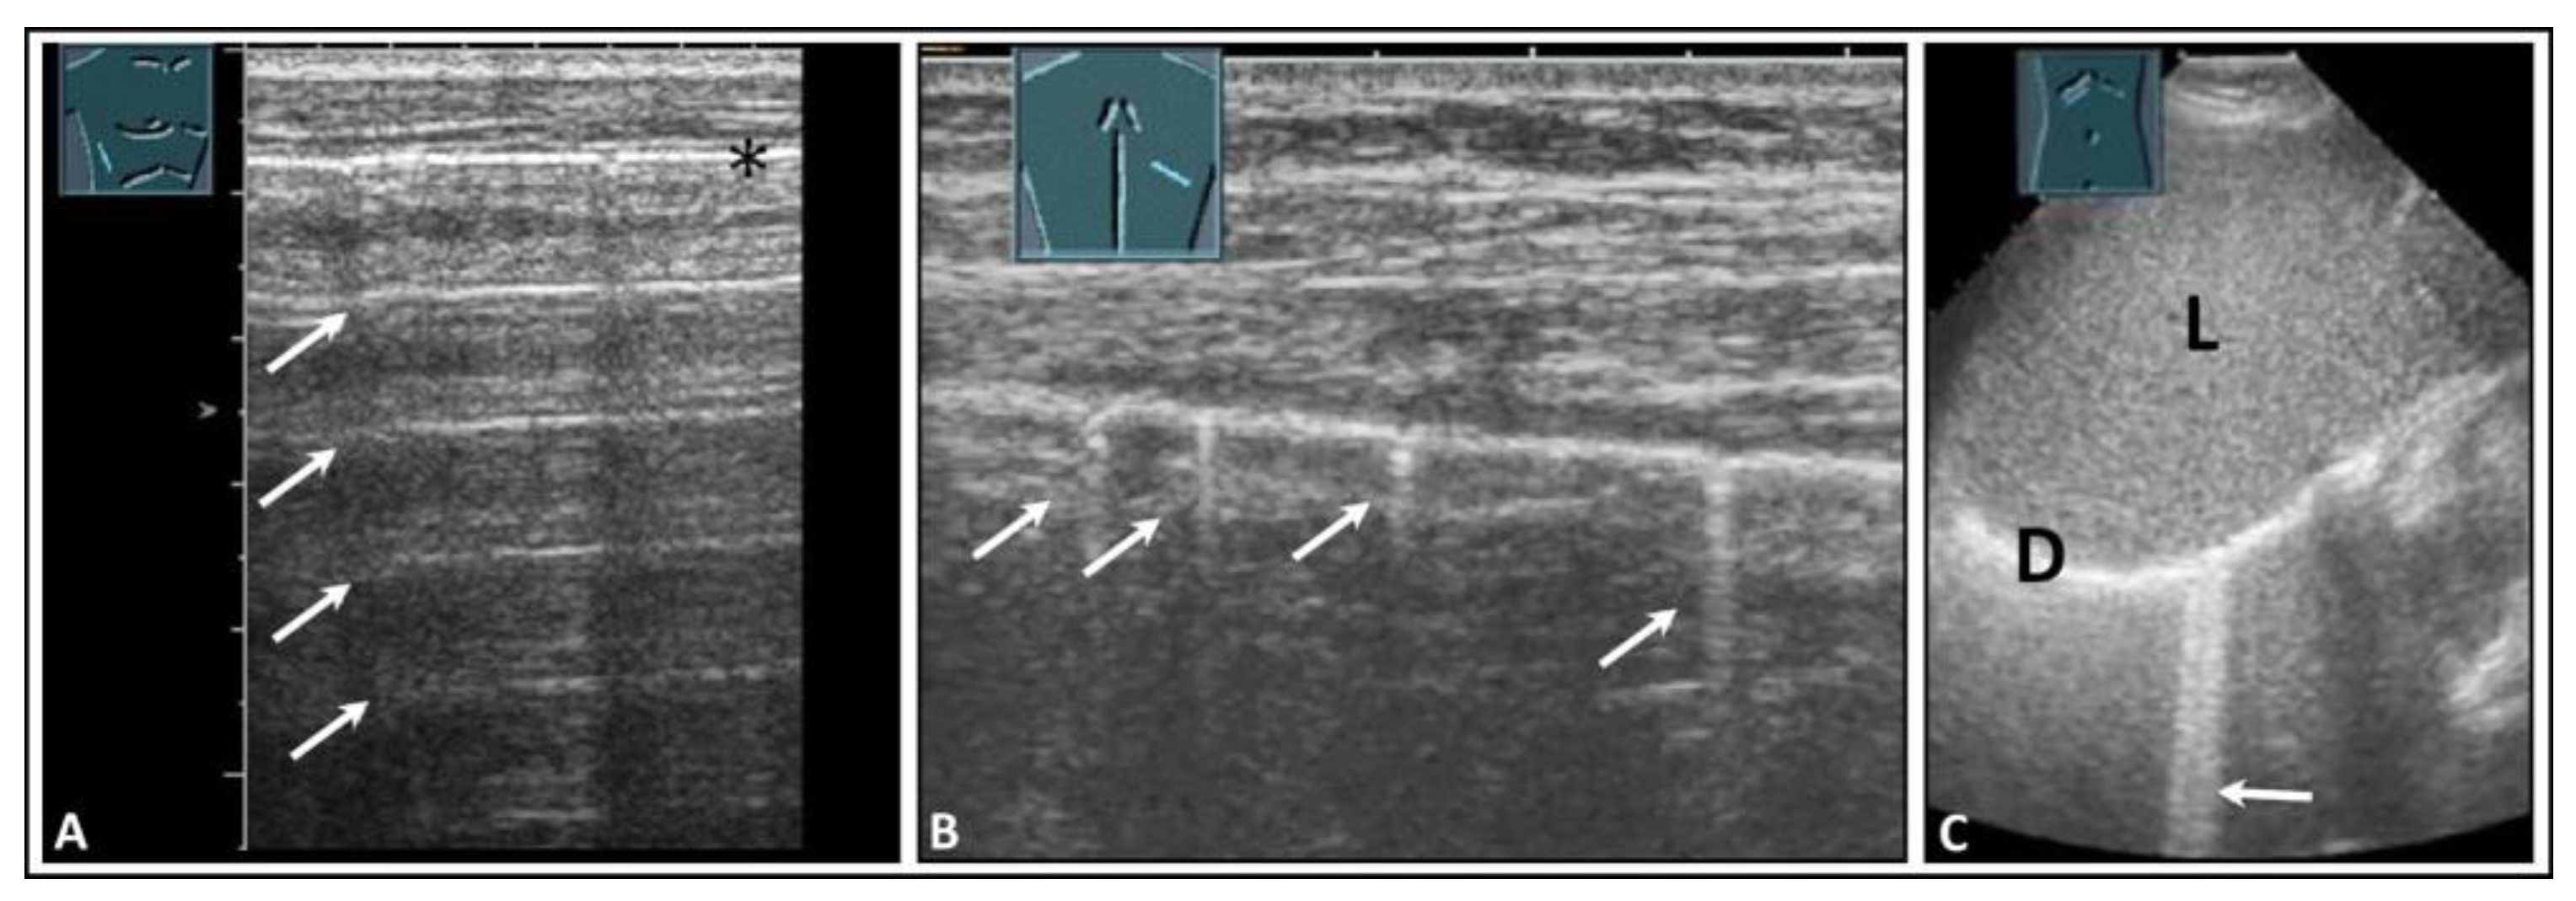

3. Underlying Pathology in Artifacts

4. Pulmonary Edema and Acute Respiratory Distress Syndrome

5. Pneumonia

6. Interstitial Lung Disease

7. Other Pathologic Situations

8. Pleural Artifacts with Simultaneous Presence of Consolidation